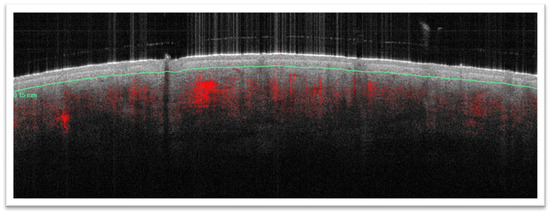

3.2. D-OCT Evaluation